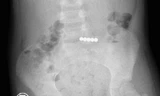

| Chuỗi nam châm hít vào nhau được phát hiện trên hình ảnh X-quang bụng của bệnh nhi |

Tuy nhiên, một tháng sau trẻ đột nhiên bị đau bụng, tình trạng diễn tiến nặng phải chuyển đến Bệnh viện Nhi Đồng Thành Phố cấp cứu. Các bác sĩ đã kiểm tra hình ảnh và phát hiện dị vật còn trong đường ruột của bệnh nhi và hít vào nhau xếp thành hình vòng tròn.